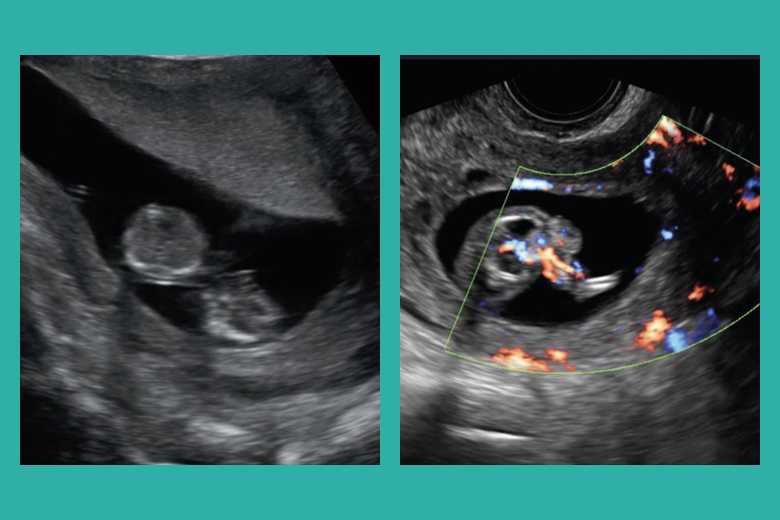

Una primigesta de 41 años con gestación doble monocoriónica bi amniótica, con diagnóstico de secuencia perfusión gemelar arterial reversa (TRAP, por sus siglas en inglés) y mal pronóstico perinatal fue intervenida mediante terapia láser intrafetal a las 18 semanas de gestación. Se complicó con rotura prematura de membranas que fue manejada en forma expectante hasta las 33 semanas 3 días, cuando se realizó cesárea electiva sin complicaciones. Se obtuvo un recién nacido vivo sano de 2,255 g que fue dado de alta hospitalaria el día 15 de nacido, sin complicaciones.

Comunicamos el primer caso de terapia láser intrafetal realizado en nuestro país y resaltamos su eficacia, sencillez, bajo costo y abordaje ambulatorio en casos de secuencia TRAP.